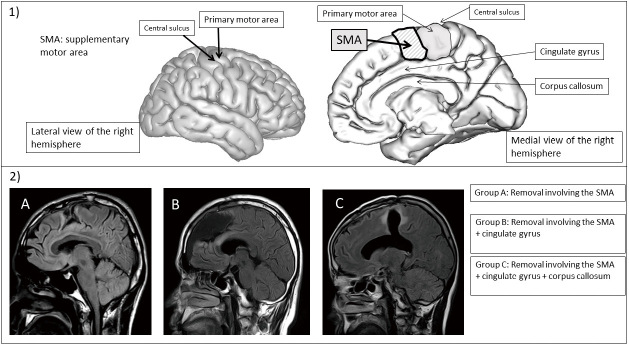

神经胶质瘤切除后辅助运动区综合征的恢复缺乏统一的观点。本研究回顾性研究了在辅助运动区附近切除肿瘤的患者中,运动功能、高级脑功能、日常生活活动能力和社会重返与肿瘤切除程度之间的关系。根据肿瘤切除的深度,我们将连续24例患者分为3组:只切除辅助运动区(5例);(B)辅助运动区和扣带回(11例);(C)辅助运动区、扣带回和胼胝体(8例)。运动麻痹、语言功能和日常生活能力在围手术期和术后2个月进行评估,而成功的社会融合则是回顾性的。C组62%的患者术后出现严重瘫痪,恢复缓慢,行动迟缓(p = 0.0869)。左半球肿瘤患者,特别是那些延伸到扣带回和胼胝体的肿瘤患者,术后单词回忆得分下降;2个月后恢复。显示日常生活能力活动的功能仪器测量评分(Functional Instrumental Measure score)在c组术前和术后差异最大。世界卫生组织肿瘤分级(p = 0.0445)和肿瘤切除程度(p = 0.0011)与术后6个月的社会融合呈负相关。总体而言,研究结果表明,早期重返社会受到世界卫生组织肿瘤分级(2021年世界卫生组织分类)和肿瘤切除程度的影响。